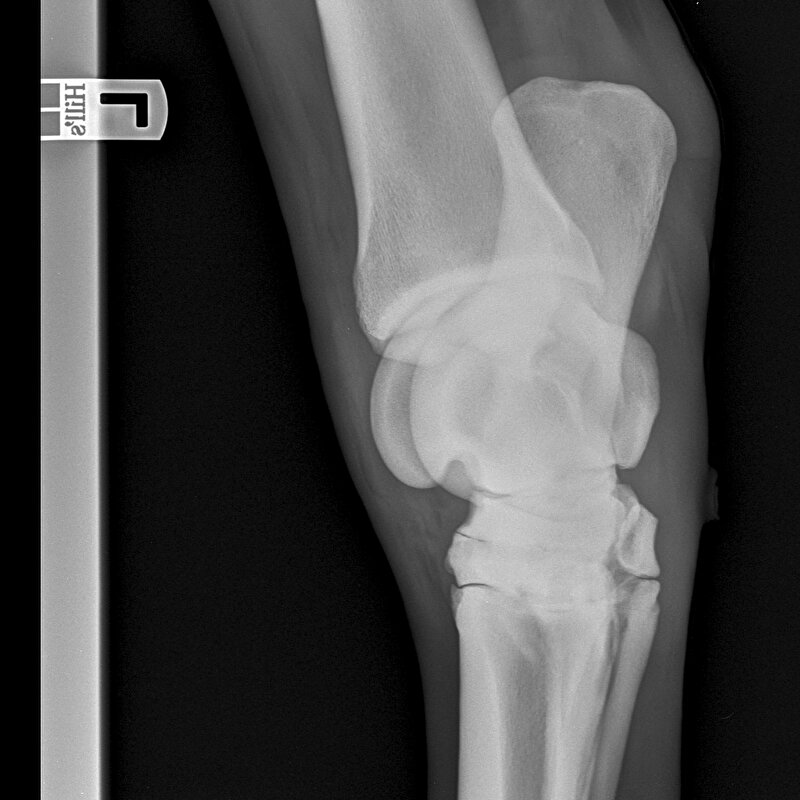

Ik heb een vraagje over röntgenfoto's. Dit gaat over een aard dat we willen kopen.

Het gaat over de sprong links achter dit paard heeft hiervoor een 3 gekregen.

Zelf heb ik geen verstand van foto's en heb ze laten beoordelen door twee artsen de eerste zegt

avulsie fragment in kogel LA in mijn optiek acceptabel beoordeling verhoogd risico.

Voor second opinion tweede arts gevraagd en die zegt ocd niet acceptabel.

Nu weet ik niet zo goed wat te doen heeft iemand ervaring met ocd?

En is het goed te verhelpen als ze er last van krijgen?

Het gaat om een fok merrie van 8 jaar niet bereden, we willen haar zowel voor fokkerij als afstandsritten rijden gebruiken.